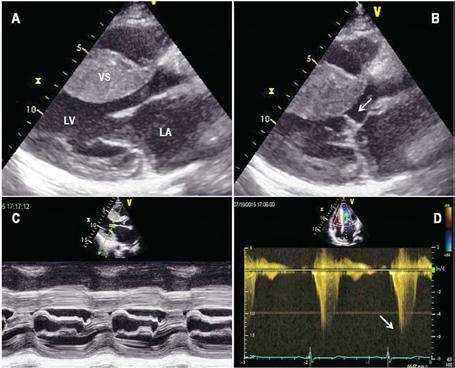

Fig.2. Ecocardiografie transtoracică – pacient sever simptomatic cu cardiomiopatie hipertrofică. (A) Sept interventricular cu hipertrofie extremă. (B) Mișcare sistolică anterioară a valvei mitrale (SAM) și contact mitro-septal. (C) Contact mitro-septal prelungit în timpul sistolei (mod M). (D) Gradient de circa 130 mmHg în tractul de ejecție al ventriculului stâng (Doppler). Adaptat după [15]

Principala metoda imagistică de evaluare și monitorizare a pacienților cu CMH este ecocardiografia bidimensională (2D).

Este esențial ca evaluările ecocardiografice să fie făcute diligent și după un protocol standard, orientarea și alinierea în planuri ortogonale trebuie să fie corecte pentru a măsura corespunzător structurile cardiace. Protocolul standard este util mai ales pentru că hipertrofia din CMH, deși interesează cel mai frecvent septul bazal, poate interesa orice segment ventricular (SIV posterior, apex VS, perete lateral)[12]. Se urmăresc parametri ca funcția sistolică și diastolică a VS, hipertrofia VS, prezența sau absența obstrucției în TEVS, volumul atriului stâng (AS), precum și date despre morfologia și funcția aparatului mitral.

Estimarea grosimii peretelui VS se face din mai multe incidențe, la sfârșitul diastolei, în secțiuni ax scurt, evitând secțiunile oblice care supraestimează hipertrofia ventriculară. Secțiunea parasternală ax lung, în modul M, ar trebui evitată pentru efectuarea măsurătorilor[13]

Conform ghidurilor de specialitate, tuturor pacienților diagnosticați cu CMH le este recomandată efectuarea ecocardiografiei 2D și Doppler, atât în repaus, cât și în timpul manevrei Valsalva – dacă gradientul de repaus este sub 50 mmHg și pacientul este simptomatic.

În cadrul urmăririi cardiologice de rutină, parte a îngrijirii optime este efectuarea de ecocardiografii transtoracice seriate. La pacienții asimptomatici, ETT se recomandă a fi repetată o dată la 1-2 ani, urmărindu-se modificări ale funcției sistolice și diastolice a VS, gradul de hipertrofie, obstrucția din TEVS, boli valvulare concomitente. Intervalul ar putea fi extins dacă pacientul rămâne clinic stabil după multiple evaluări[6]

Fiziopatologia care contribuie la obstrucția TEVS (Fig.2) include anomalii interconectate precum hipertrofia asimetrică a VS, SAM, hipertrofia mușchilor papilari cu sau fără deplasarea acestora, inserții anormale ale mușchilor papilari, cât și modificări la nivelul cuspelor valvei mitrale (VM)[14]

Fig.3. Ecocardiografie transesofagiană în cardiomiopatie hipertrofică obstructivă, ce remarcă obstrucția tractului de ejecție al ventriculului stâng (VS) prin contact mitro-septal (sus, săgeată) și regurgitare mitrală importantă (jos) ETE efectuată perioperator (Fig.3) este însă esențială pentru ghidarea strategiei chirurgicale în cazul miectomiei chirurgicale,

3. Rezonanța magnetică cardiacă

RMc oferă informații despre morfologia cardiacă, funcția ventriculară și caracteristicile miocardului ventricular[18]. Evaluarea prin această tehnică a pacienților cu CMH diagnosticată sau suspectată ar trebui făcută ținând cont de recomandările ghidurilor de specialitate și ar trebui realizată și interpretată de echipe cu experiență în imagistica cardiacă și în evaluarea cardiomiopatiilor.

RMc reprezintă standardul de aur pentru cuantificarea volumelor și maselor ventriculare, fibrozei și a fracției de ejecție. Evaluarea globală și regională a funcției contractile a VS, distribuția și extensia hipertrofiei și a fibrozei, anatomia și fiziologia VM – sunt elemente cheie în stabilirea unui diagnostic cert, a prognosticului și pentru elaborarea planului terapeutic. Astfel, RMc ar trebui efectuată încă de la evaluarea inițială. Despre morfologia și funcția VS, la pacienții cu fereastră ecocardiografică bună, se pot obține informații similare prin cele două tehnici[19]. Dacă anumite segmente ventriculare sunt greu vizualizabile, cum ar fi peretele antero-lateral sau apexul VS și VD, imagistica prin RM poate aduce informațiile lipsă, necesare diagnosticului[20]

Tot imagistica radiomagnetică este utilă în evaluarea pacienților înainte de miectomia septală și poate îndruma atitudinea terapeutică deoarece poate descrie anumite caracteristici care sunt relevante pentru strategia chirurgicală, incluzând distribuția precisă a hipertrofiei septale (Fig.4), anomalii ale VM și ale aparatului subvalvular, poziționarea anormală a mușchilor papilari,

conexiuni aberante ale cordajelor, cât și anomalii ale căii de ieșire din VD. RMc poate fi folosită, utilizând proprietățile magnetice intrinseci ale țesutului miocardic și distribuția substanței de contrast pe bază de gadoliniu, pentru a detecta zonele de fibroză de la nivelul interstițiului miocardic. Captarea tardivă a gadoliniului (LGE) este utilizată pentru a diferenția miocitele normale, arhitectura acestora și ariile de fibroză. Din cauza heterogenității CMH, au fost descrise multiple modele de captare tardivă a gadoliniului: LGE subendocardică, transmurală, difuză. La 65% din pacienții cu CMH, LGE este prezentă având în mod tipic o distribuție neuniformă în zonele de hipertrofie care tind să se coreleze cu zonele de anomalii de contractilitate parietală. Fibroza este localizată mai ales în treimea medie a VS, având o distribuție multifocală, însă și VD poate fi implicat.

Extensia LGE este un marker al anomaliilor de deplasare ale pereților ventriculari și este asociată cu creșterea rigidității miocardice și cu remodelarea ventriculară avansată. Aprecierea gradului de fibroză septală prin identificarea LGE, poate fi utilă în alegerea conduitei terapeutice, înaintea tratamentului invaziv al înlăturării obstrucției din TEVS[24]

Fig.4. Cuantificarea exactă a distribuției și dimensiunilor hipertrofiei septale în diferite secțiuni de rezonanță magnetică cardiacă.